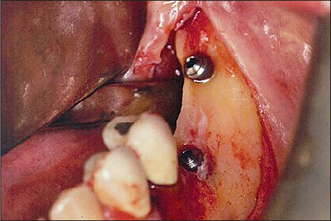

Second-stage surgery to expose an implant

After the healing phase is complete it can sometimes be difficult to determine the exact location of a two-stage (submucosal) implant. A dental probe can be used to palpate the cover screw through the anaesthetized tissues. Once the cover screw is located, a crestal incision is made to expose it (Fig. 11.30). The cover screw is then removed and a healing abutment inserted. If necessary, resorbable sutures are placed to ensure close apposition of the oral mucosa to the healing abutment (Fig. 11.31). After a period of 7–10 days, the healing abutment is replaced with a suitable abutment that will subsequently be loaded.

image

Fig. 11.30 Second-stage surgery. The cover screw is exposed via a small incision.

Fig. 11.31 A healing abutment is placed to ensure good healing of oral mucosa to the surface of the abutment.